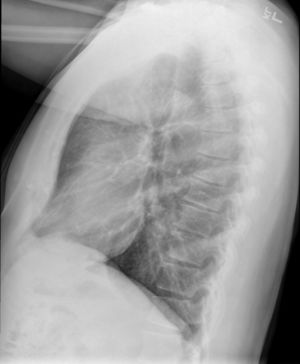

Causes include breathing in toxic fumes, respiratory infections, connective tissue disorder or complications following a bone marrow or heart-lung transplant.[1] Symptoms may not occur until two to eight weeks following toxic exposure or infection.[1] The underlying mechanism involves inflammation that results in scar tissue formation.[1] Diagnosis is by CT scan, pulmonary function tests or lung biopsy.[1] A chest X-ray is often normal.[4]

Obliterative bronchiolitis is often diagnosed based on the symptoms of obstructive lung disease following lung injury. The definitive diagnosis is through biopsy, but due to the variable distribution of lesions, leading to falsely negative tests, and invasive nature of this procedure it is often not performed.[6][11] Several tests are often needed to diagnose obliterative bronchiolitis, including spirometry, diffusing capacity of the lung tests (DLCO), lung volume tests, chest X-rays, high-resolution CT (HRCT), and lung biopsy.[11][4]

Medical imaging

Early in the disease chest radiography is typically normal but may show hyperinflation.[6] As the disease progresses a reticular pattern with thickening of airway walls may be present.[4][6] HRCT can also show air trapping when the person being scanned breathes out completely; it can also show thickening in the airway and haziness in the lungs.[11] A common finding on HRCT is patchy areas of decreased lung density, signifying reduced vascular caliber and air trapping.[6] This pattern is often described as a "mosaic pattern", and may indicate obliterative bronchiolitis.[6]